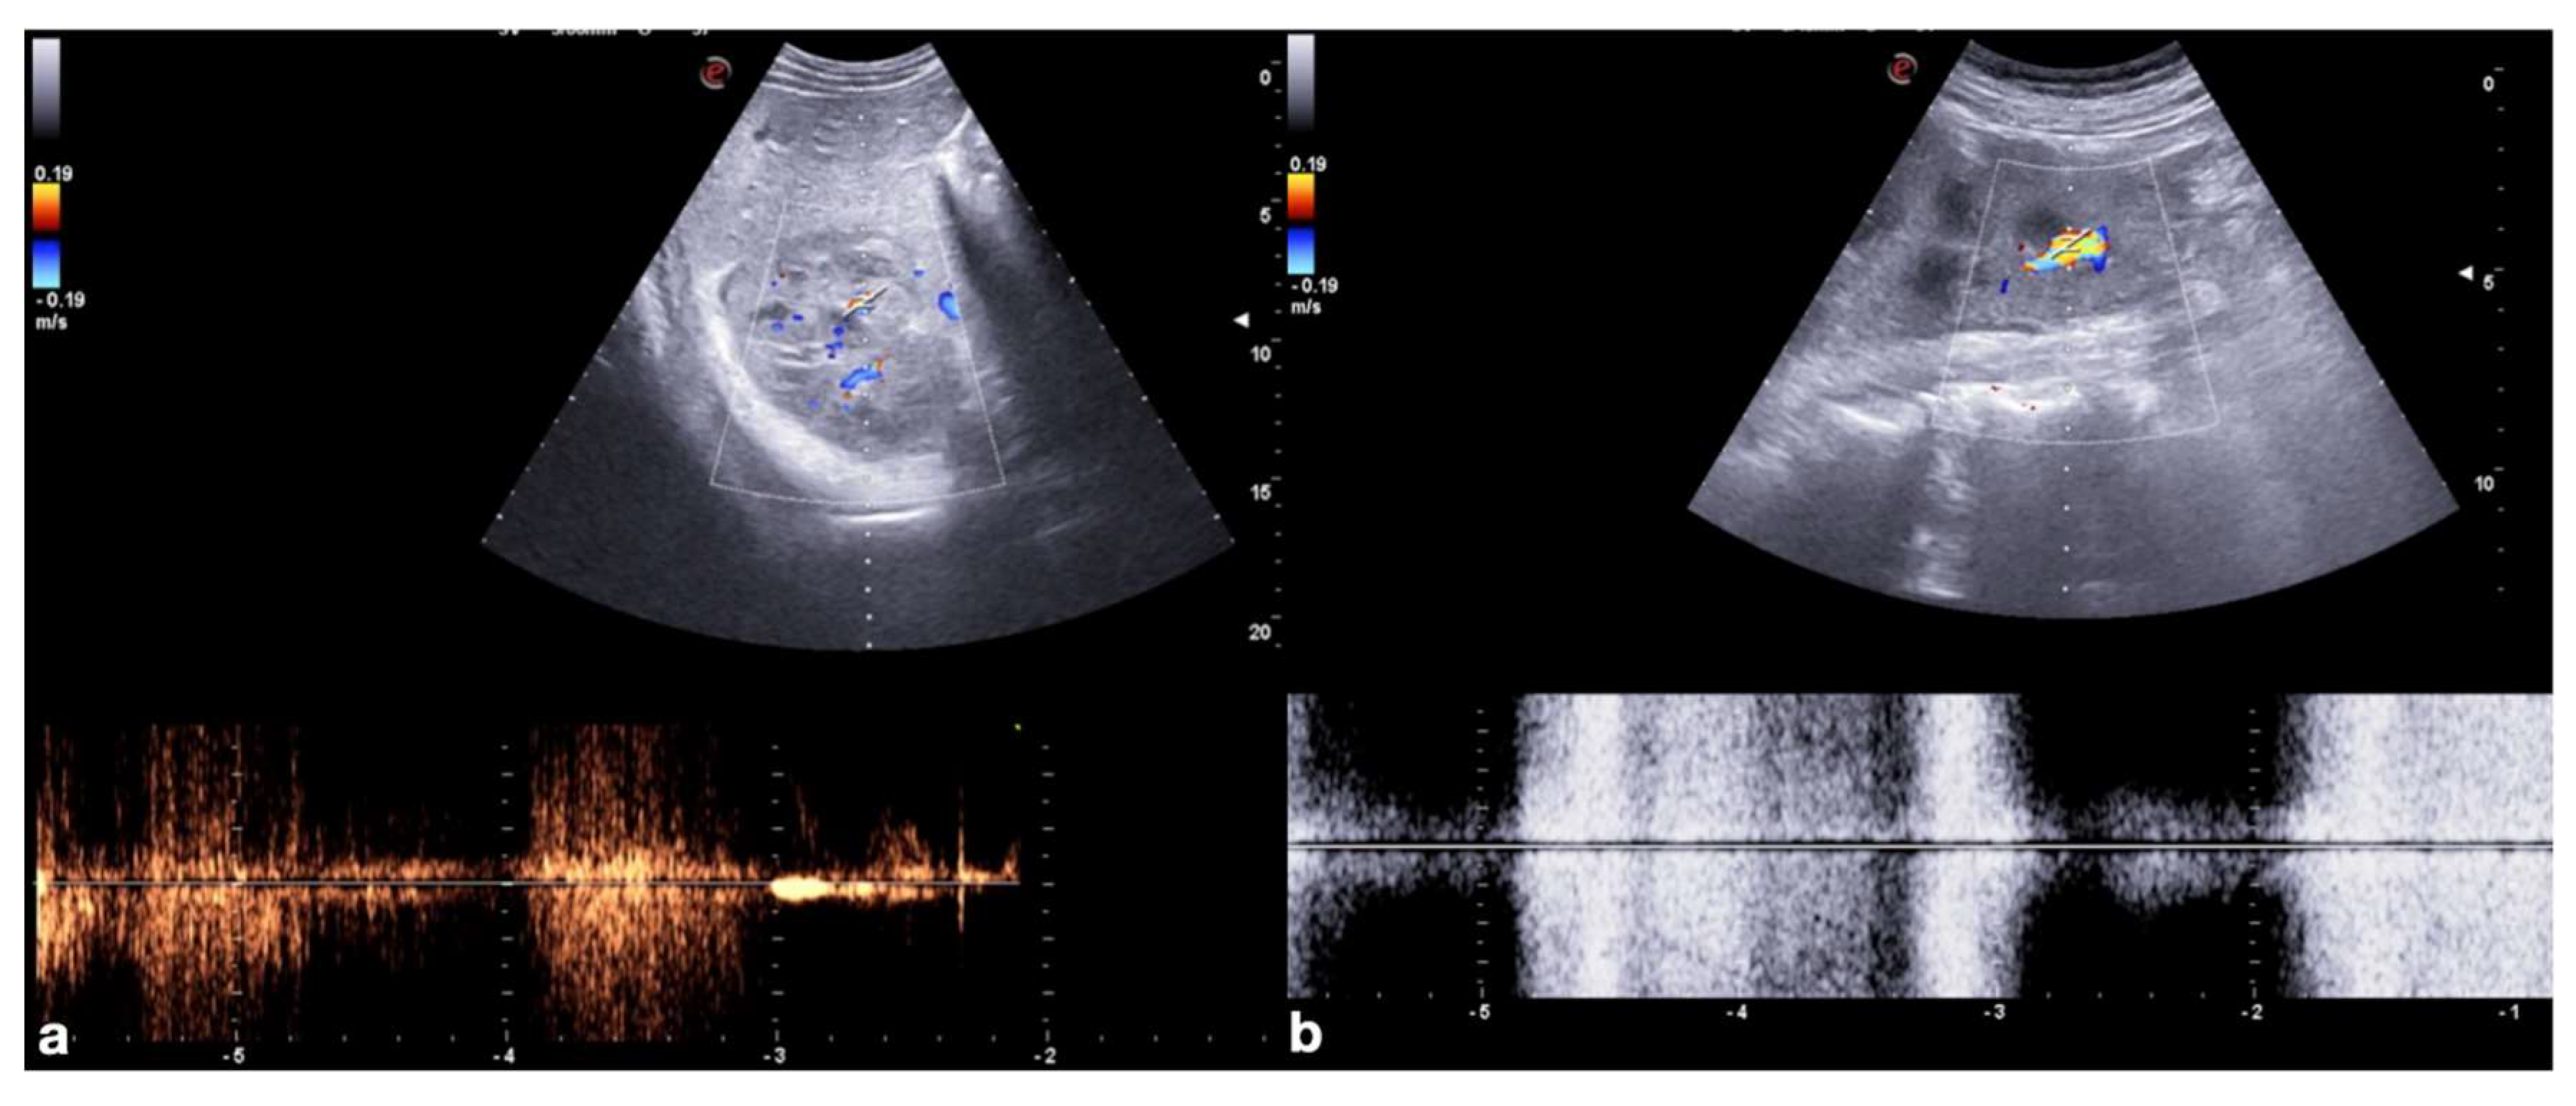

The administration of the UCA should be preceded by a preliminary study with a color and power Doppler US (CD–US) of the injured parenchyma to identify any contained vascular lesions. This increases the diagnostic confidence in differentiating these lesions through their characteristic spectral pulsed-wave Doppler (Figure 2).

Figure 2.

Role of color and spectral Doppler in the detection of post-traumatic vascular complications. Color (upper row) and spectral (bottom row) Doppler of the right kidney show post-traumatic pseudo-aneurysm in a 20−year-old man admitted to the emergency department for hematuria two weeks after a car accident and previous CT diagnosis of traumatic right kidney contusion (a); color Doppler shows turbulent flow in the false aneurysm, whereas spectral Doppler shows a “to and fro” spectrum. Color (upper row) and spectral (bottom row) Doppler of left kidney show post-traumatic arteriovenous fistula in a 45−year-old woman admitted at emergency department for penetrating injury (b); color Doppler shows aliasing artifact due to the presence of a focus of increased blood flow, then confirmed at pulsed Doppler that shows high-velocity peak without a clear diastolic flow.

Indeed, after UCA administration, these lesions could become indeterminate at CD–US evaluation due to the relative turbulence generated by the micro-bubbles; furthermore, the relative destruction of the micro-bubbles due to high MI during the Doppler study may also render the contrast study ineffective (Figure 3).

Figure 3.

Artifacts in color and spectral Doppler after CEUS (a,b), and in repeated CEUS after Doppler (c,d). Mesenteric artery color and spectral Doppler before (a) and after (b) UCA administration showed alteration in the color map (upper row) as well as in the waveform (bottom row) evaluation due to the relative turbulence generated by the micro-bubbles within the vessel. Upper abdomen CEUS in pancreatic trauma before (c) and after (d) Doppler study shows relative destruction of the micro-bubbles due to high MI during the Doppler study, making the post-Doppler contrast study unable to visualize organs and tissues properly.